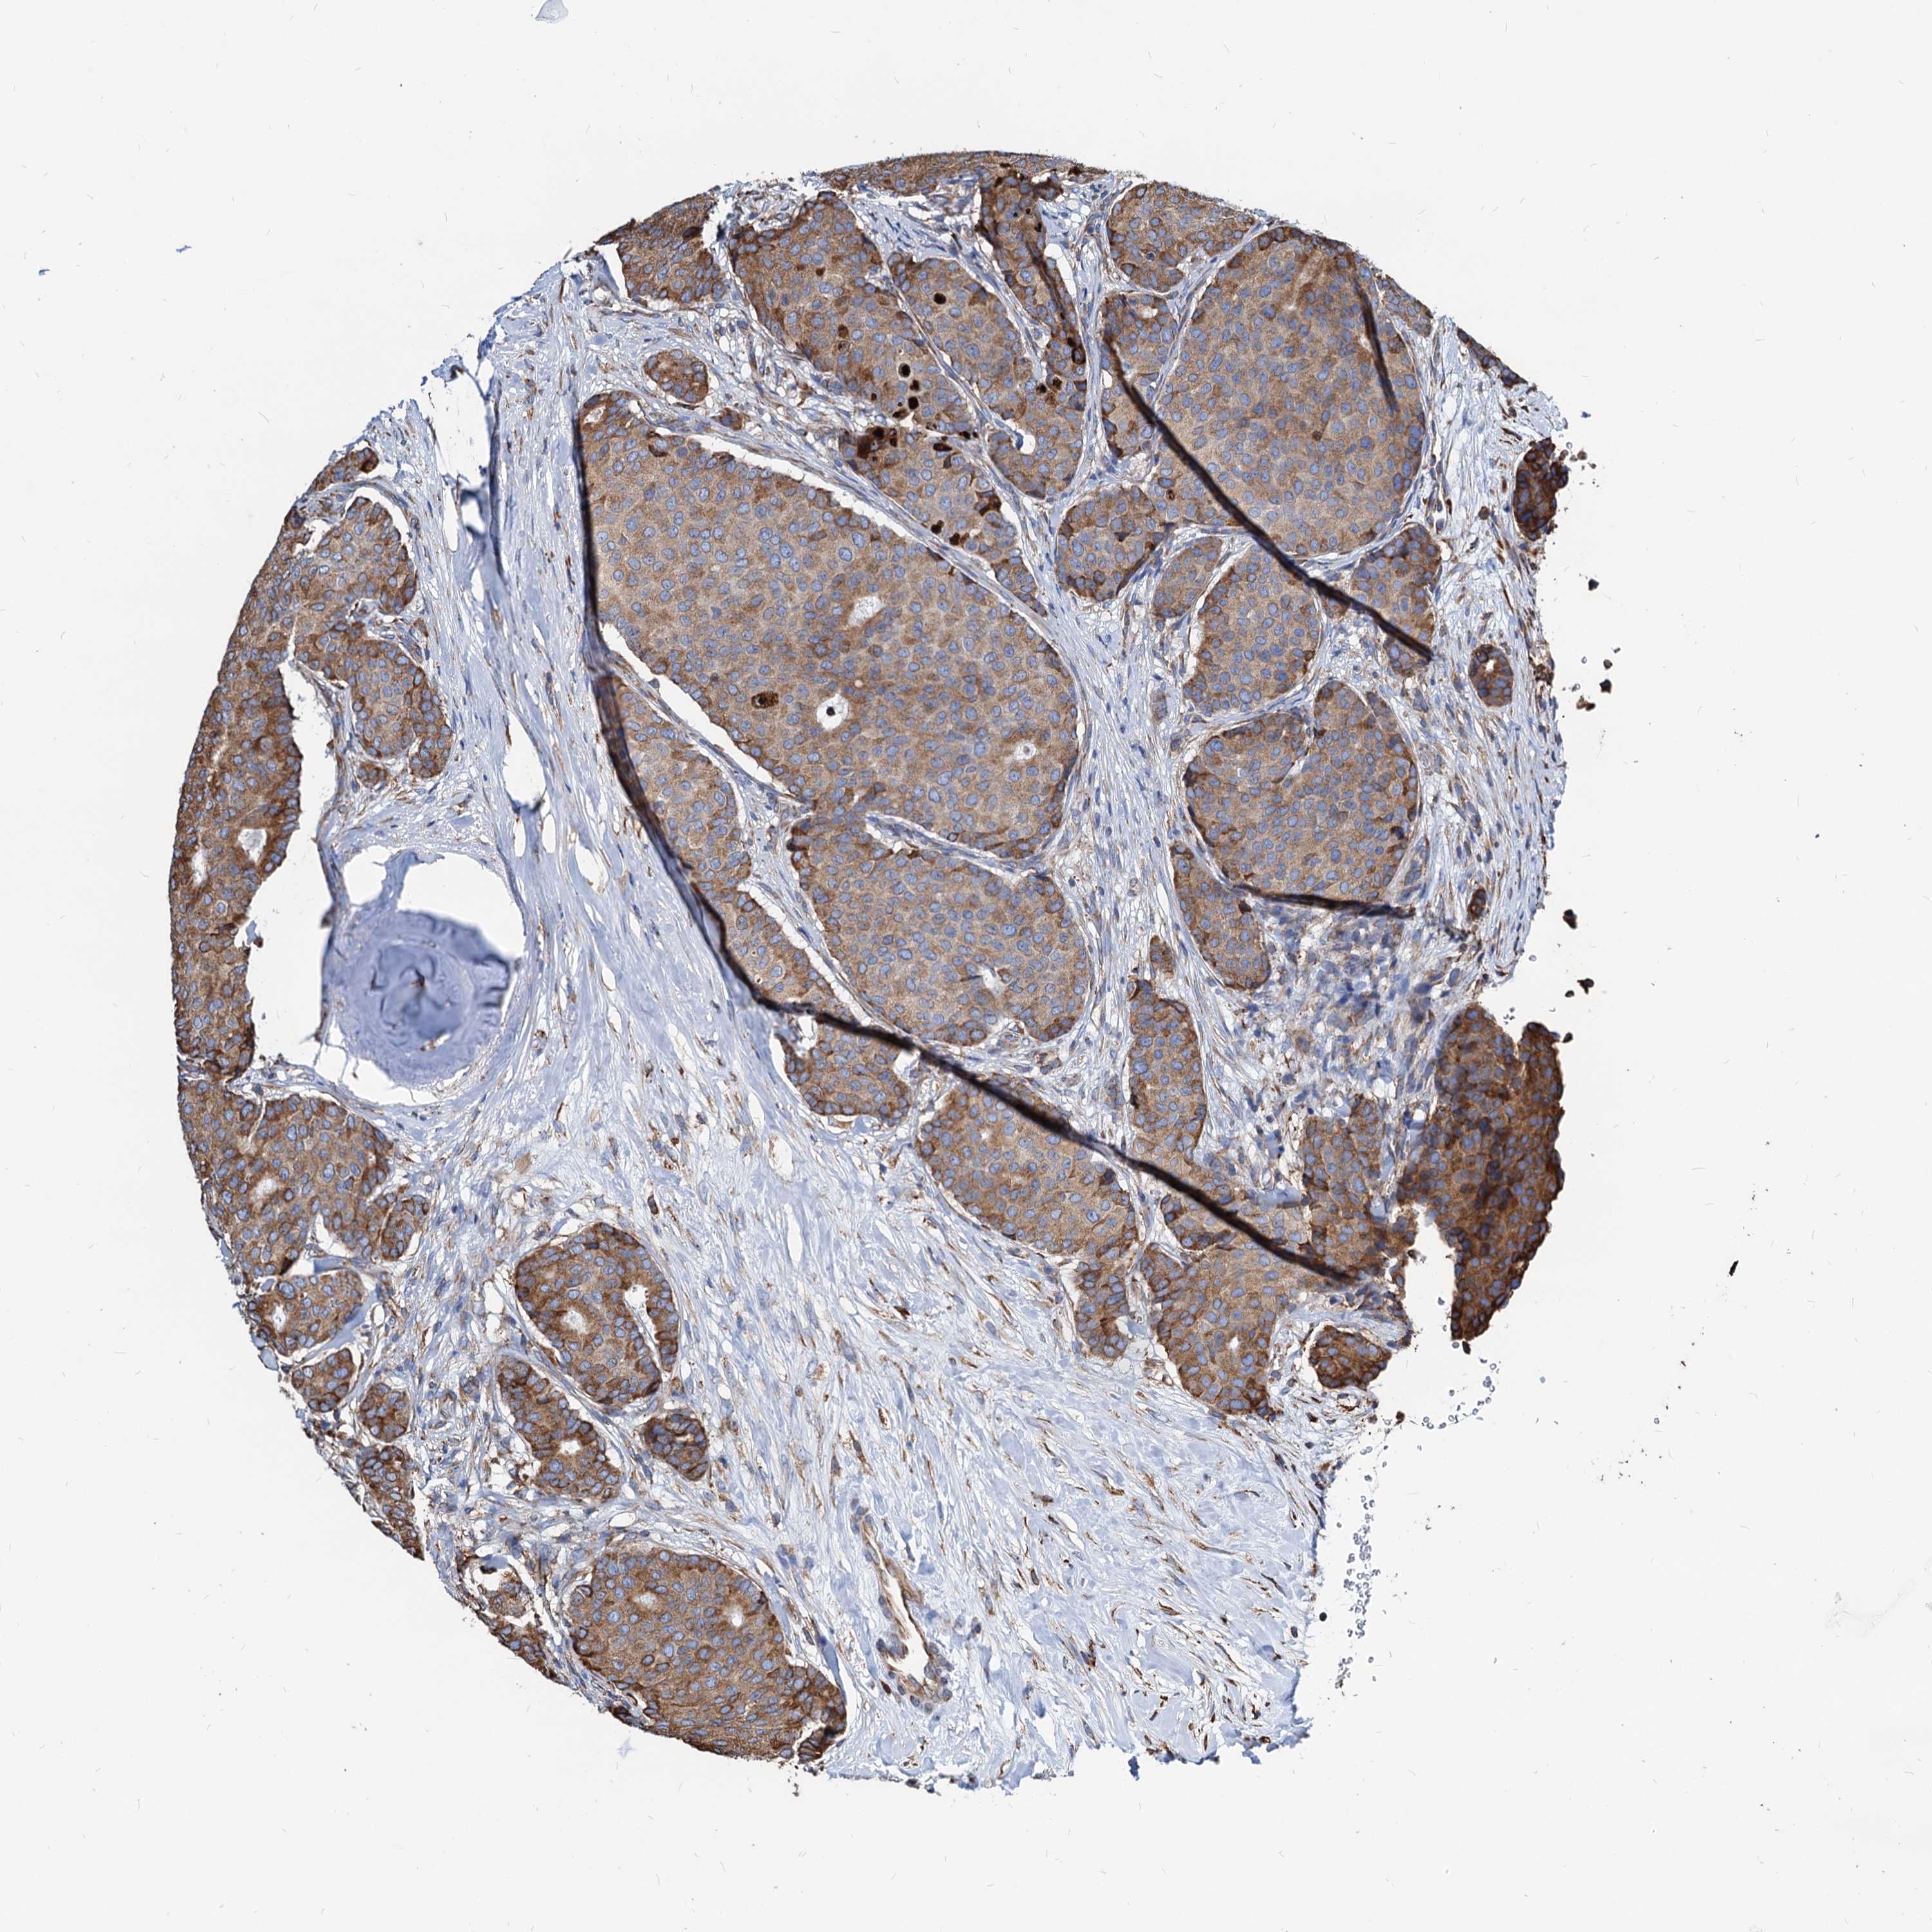

CANCER BREAST CANCER Show tissue menu

BRCA TCGA BRCA VALIDATION PROTEIN EXPRESSION

Breast cancer

Human cancer